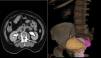

TAC de abdomen simple y contrastada: riñón derecho con hidronefrosis, con uréter dilatado y tortuoso en todo su trayecto, que se inserta en la vejiga en la porción que está prolapsada. Se aprecia prolapso del piso pélvico, con la vejiga urinaria de 6cm por debajo de la sínfisis del pubis, descenso del recto y del segmento inferior del útero. Quistes renales simples bilaterales, derecho de 16.2mm e izquierdo de 22mm (fig. 2).